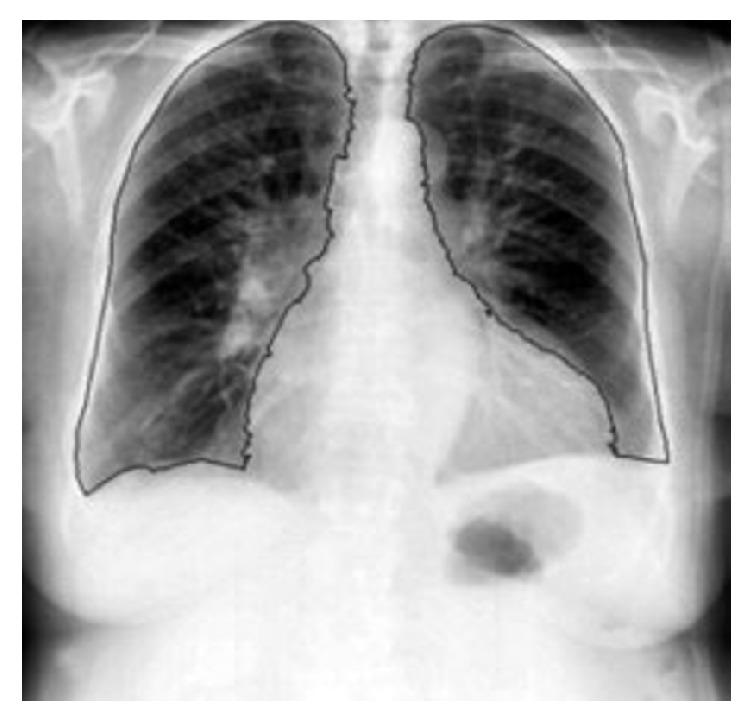

综述:关于从前后位胸部X光片中分割结节

Review: On Segmentation of Nodules from Posterior and Anterior Chest Radiographs.

Lung cancer is one of the major types of cancer in the world. Survival rate can be increased if the disease can be identified early. Posterior and anterior chest radiography and computerized tomography scans are the most used diagnosis techniques for detecting tumor from lungs. Posterior and anterior chest radiography requires less radiation dose and is available in most of the diagnostic centers and it costs less compared to the remaining diagnosis techniques. So PA chest radiography became the most commonly used technique for lung cancer detection. Because of superimposed anatomical structures present in the image, sometimes radiologists cannot find abnormalities from the image. To help radiologists in diagnosing tumor from PA chest radiographic images range of CAD scheme has been developed for the past three decades. These computerized tools may be used by radiologists as a second opinion in detecting tumor. Literature survey on detecting tumors from chest graphs is presented in this paper.

肺癌是全球主要的癌症类型之一。如果能早期发现该疾病,生存率可以提高。胸部前后位X线摄影和计算机断层扫描是检测肺部肿瘤最常用的诊断技术。胸部前后位X线摄影所需辐射剂量较少,在大多数诊断中心都可进行,且与其他诊断技术相比成本较低。因此,胸部后前位X线摄影成为肺癌检测最常用的技术。由于图像中存在重叠的解剖结构,有时放射科医生无法从图像中发现异常。在过去三十年里,为帮助放射科医生从胸部后前位X线摄影图像中诊断肿瘤,已经开发了一系列计算机辅助检测(CAD)方案。这些计算机化工具可被放射科医生用作检测肿瘤的第二种意见。本文介绍了关于从胸部X线片检测肿瘤的文献综述。